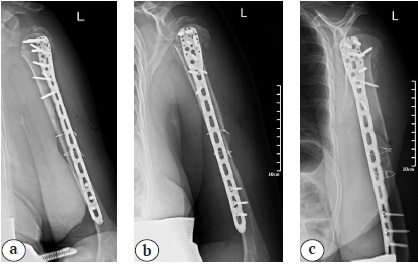

The control X-rays showed a consolidated fracture of the humeral diaphysis 9 months postoperatively, as well as the development of avascular necrosis of the left humeral head, nonunion, and migration of the greater tubercle into the subacromial space (Fig. 4). The shoulder function was limited, and the pain syndrome up to 5 VAS points persisted during movements, as well as a pronounced limitation of the amplitude of active movements with the abduction of up to 70°, flexion of up to 90°, external rotation of up to 0°, and internal rotation at the L5 level. However, the patient was fully adapted to daily activities.

Fig. 4. Shoulder control X-ray after 9 months since surgery: consolidation of the diaphyseal part, nonunion, secondary displacement of the greater tubercle and avascular necrosis of the humeral head